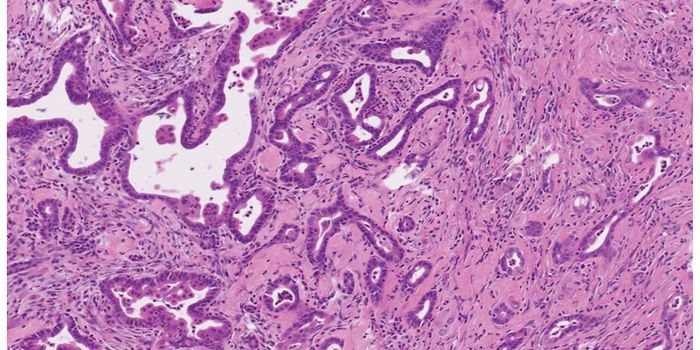

Follow a curation of discoveries and updates in immunology focusing on immune responses to infectious disease, structure and function, and developments in the defense against infection.